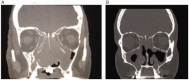

Results: A total of 356 patients had scans available for review; 80 (23%) patients were categorized into the AFRS group, 101 (28%) in the AERD group, 43 (12%) in the CCAD group, and 132 (37%) in the CRSwNP NOS group. Septal inflammatory involvement and oblique middle turbinate orientation on CT scans was higher in both AERD patients and CCAD patients as compared to AFRS and CRSwNP NOS patients (P < .05). Olfactory cleft opacification was increased in the AERD group compared to all other diagnoses (P < .05). The CCAD group showed lower LM scores compared to all other groups (P < .05), and the AFRS group revealed the greatest differences between left and right LM grades, representing unilaterality of disease (P < .05).